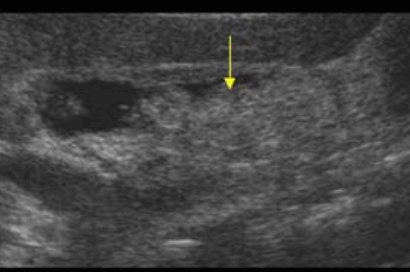

US finding

- 담즙으로부터 침전된 작은 미립자 물질의 혼합물

- 균일한 중간에코로 보이며 후방음향음영이 없다(결석과의 감별)

- 환자체위 변화로 인한 이동성 (용종과의 감별)

- sludge ball (=tumefactive sludge) 종양형 담즙앙금은 color doppler vascularity 유무로 종양과의 감별을 요한다